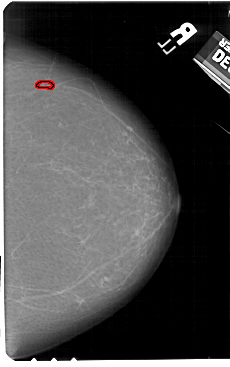

A_1601_1.LEFT_MLO

LEFT_MLO LINES 5251 PIXELS_PER_LINE 3406 BITS_PER_PIXEL 12 RESOLUTION 43.5 NON_OVERLAY

RIGHT_MLO LINES 5461 PIXELS_PER_LINE 3601 BITS_PER_PIXEL 12 RESOLUTION 43.5 OVERLAY

FILE: A_1601_1.RIGHT_MLO.OVERLAY

TOTAL_ABNORMALITIES 1

ABNORMALITY 1

LESION_TYPE CALCIFICATION TYPE PLEOMORPHIC DISTRIBUTION LINEAR

ASSESSMENT 4

SUBTLETY 2

PATHOLOGY BENIGN

TOTAL_OUTLINES 1

BOUNDARY